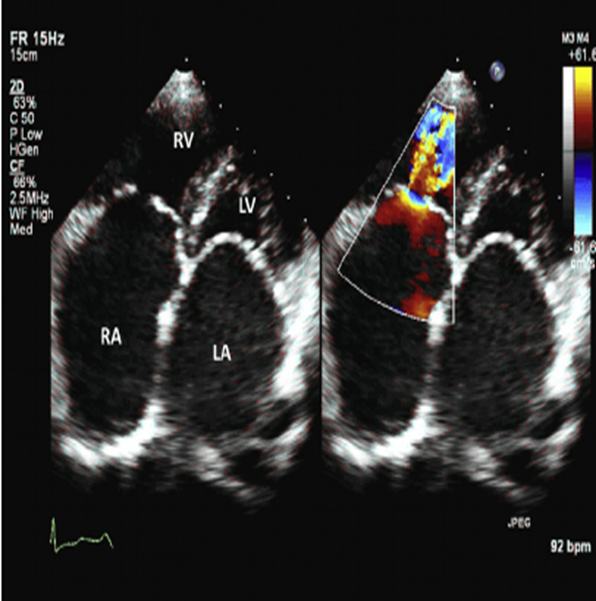

Asses RVIT

Asses apical 4

What happens during Tricuspid Regurgitation?

As the right ventricle contracts to pump blood forward to the lungs, some blood leaks backward into the right atrium, increasing the volume of blood in the atrium.

As a result of TR..

As a result, the right atrium can enlarge, which can change the pressure in the nearby chambers and blood vessels.

-Enlarged RA, RV, IVC, Hepatic veins, SVC & Neck veins

Tricuspid Regurgitation Color Jet

Assess TR jet width and length in all views. Adjust color gain, scale, and color box

Views in RVIT, SAX AO, A4C